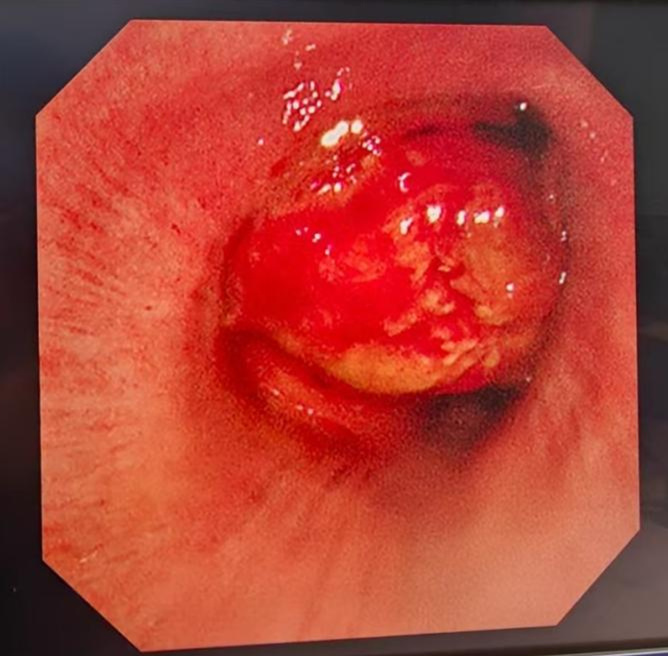

一小时后,手术开始。术者插入硬质气管镜检查,可见肿瘤压迫主气管,其狭窄程度高达90%,左支气管完全堵塞。如患者延迟手术,则有极大可能肿瘤完全堵塞气管导致窒息。

术中气管镜下显示肿瘤基本完全堵塞气管管腔。